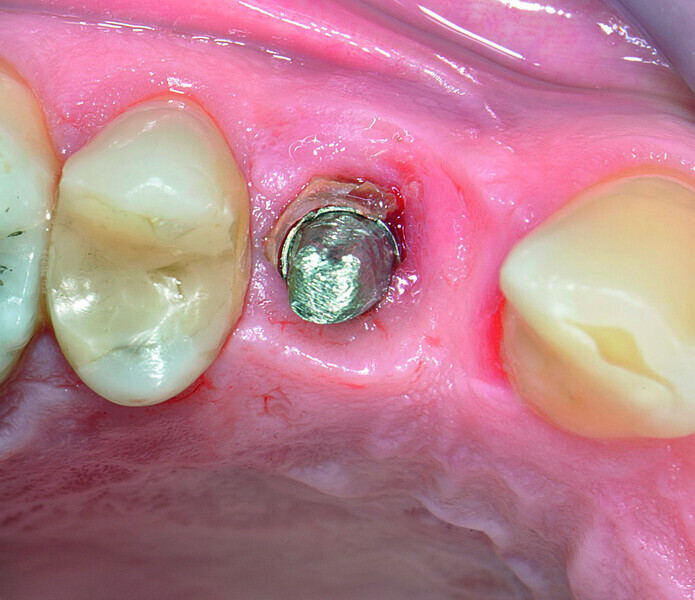

Fig. 3: Excess resin cement around the implant.